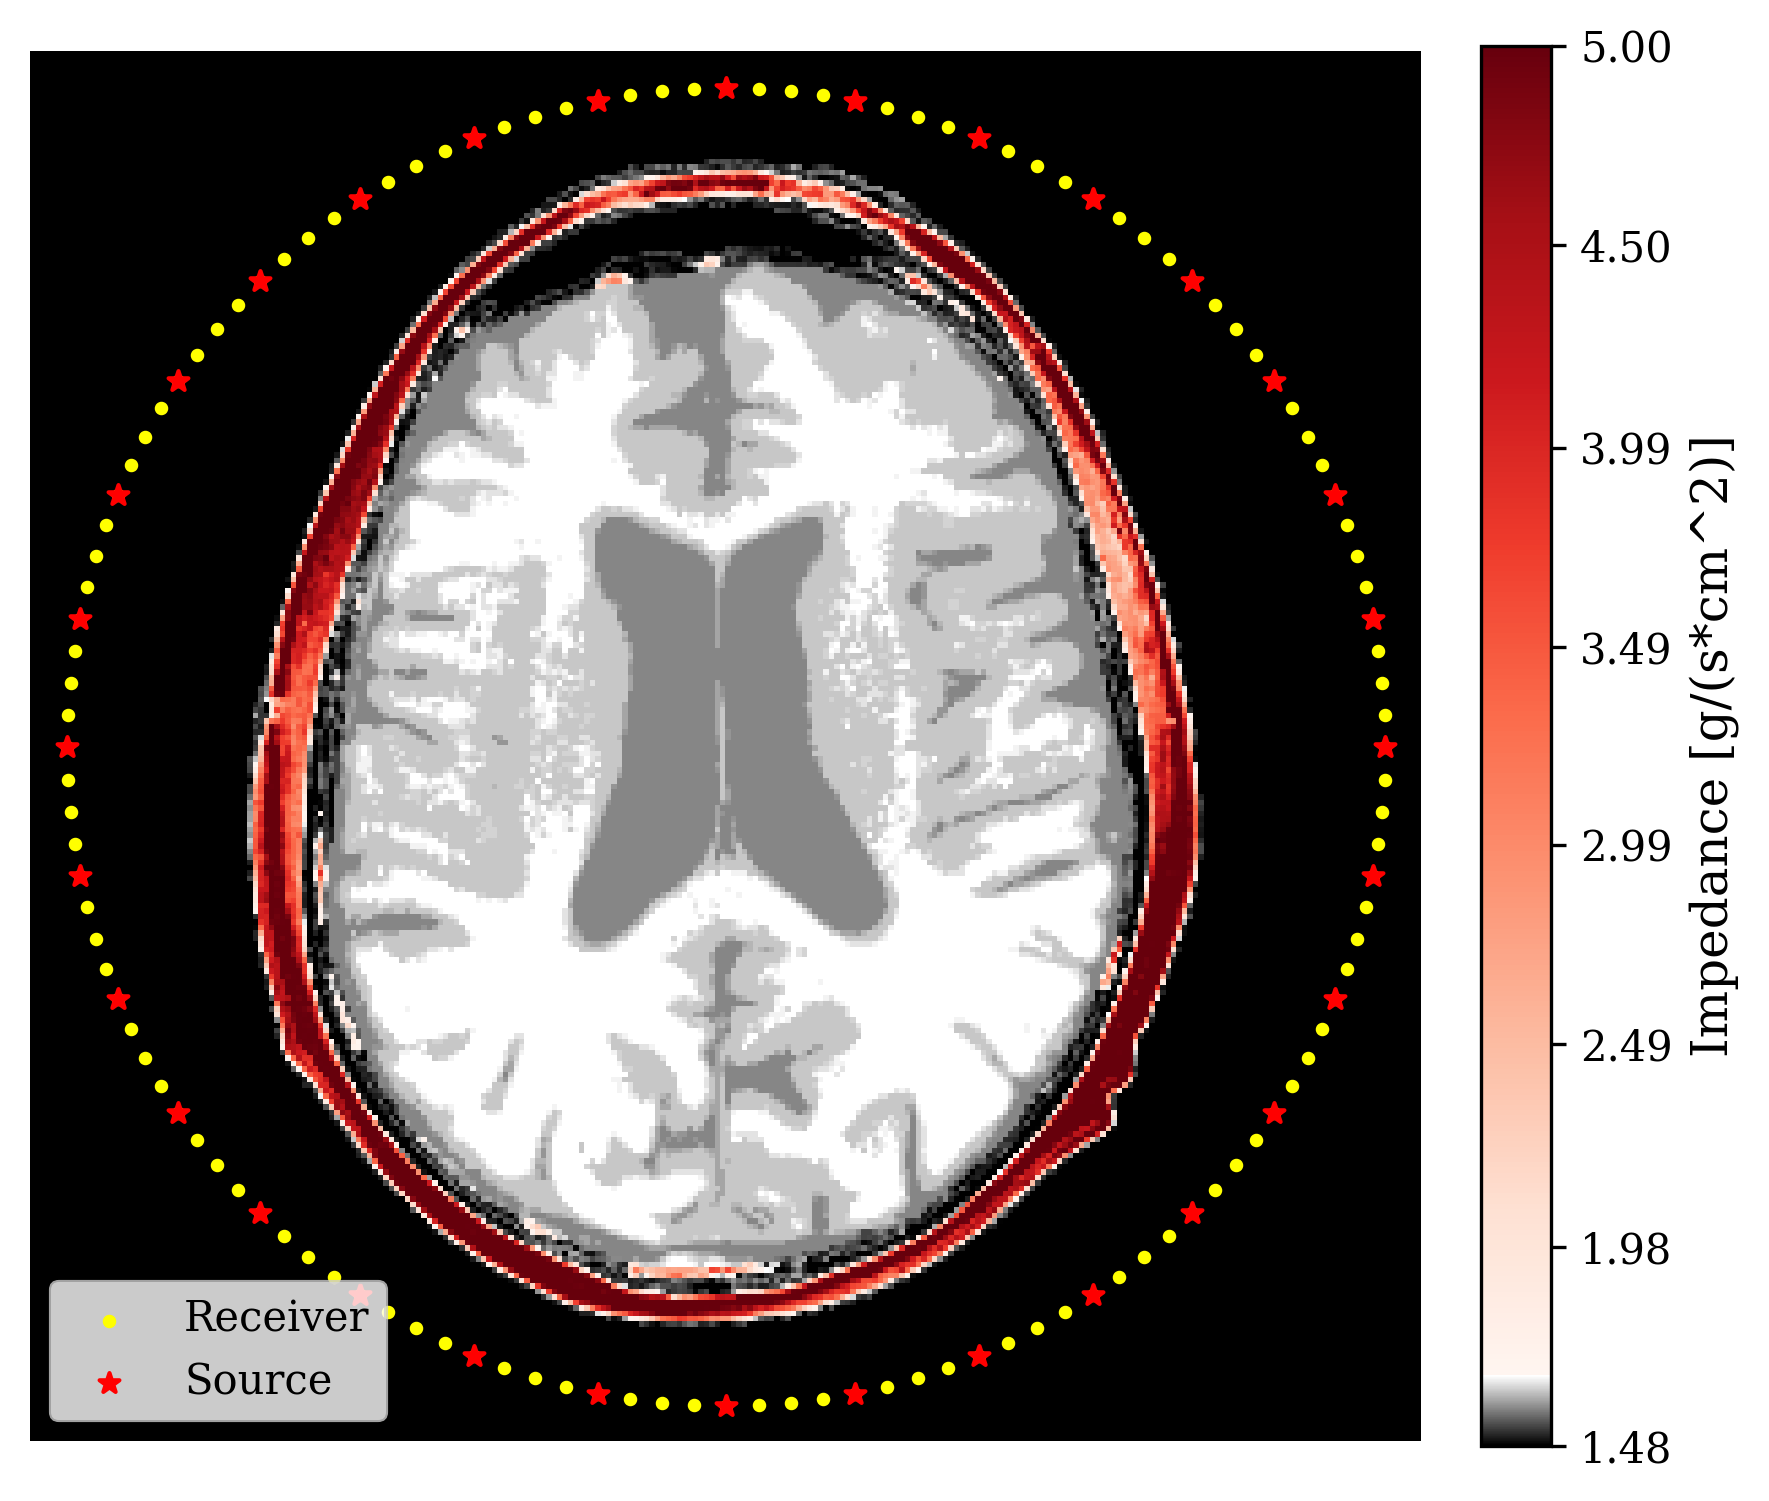

with being the full observation over sources. To account for errors in the measurements, an additive noise term is included as . Typical 3D hardware setups have sources and for our 2D simulation we use up to sources. This makes the full observation . Figure 2 shows data of a single source experiment with the acoustic impedance shown in Figure 2. In our setup, we model transducer receivers around the skull, of which also act as sources. They record for time steps. Given observed transcranial ultrasound data, , our aim is to invert for internal structures . We solve this inverse problem in a Bayesian framework so uncertainty due to incomplete measurements, modeling errors, and noise, can be quantified systematically.

where is a starting point at which the gradient is calculated. Note, \equationrefeq:summ-data involves evaluating the forward physical model and its Jacobian adjoint . Thus this summary is informed by the physics (domain knowledge). As a result, the summarized data lives in the reduced image space (reduction factor of about ). According to Fluri et al. (2021), the informativeness of this summary statistic also implies that thus we propose to use the same conditional distribution learning objective as \equationrefeq:train-cond but replace the data with the summary . See Algorithm 1 in the Appendix for our full training process. The technical assumptions for the informativeness of this summary statistic are discussed in Appendix 4.5 alongside studies to understand the effect of deviations from the assumptions. One of the assumptions is that the starting point needs to be carefully chosen as it will affect how informative the summary statistic will be. For our application, is the acoustically correct model of the skull bone and a constant acoustic model inside the skull since the soft tissues inside the skull are the clinically relevant structures we care to image. Inclusion of the skull is needed so that the physical operators create meaningful results that inform the posterior. In practice, acoustic values of skull bone can be calculated from CT scans Aubry et al. (2003). See Figure 2 for an example of and Figure 2 for the physics-informed summary it creates.

\subfigure